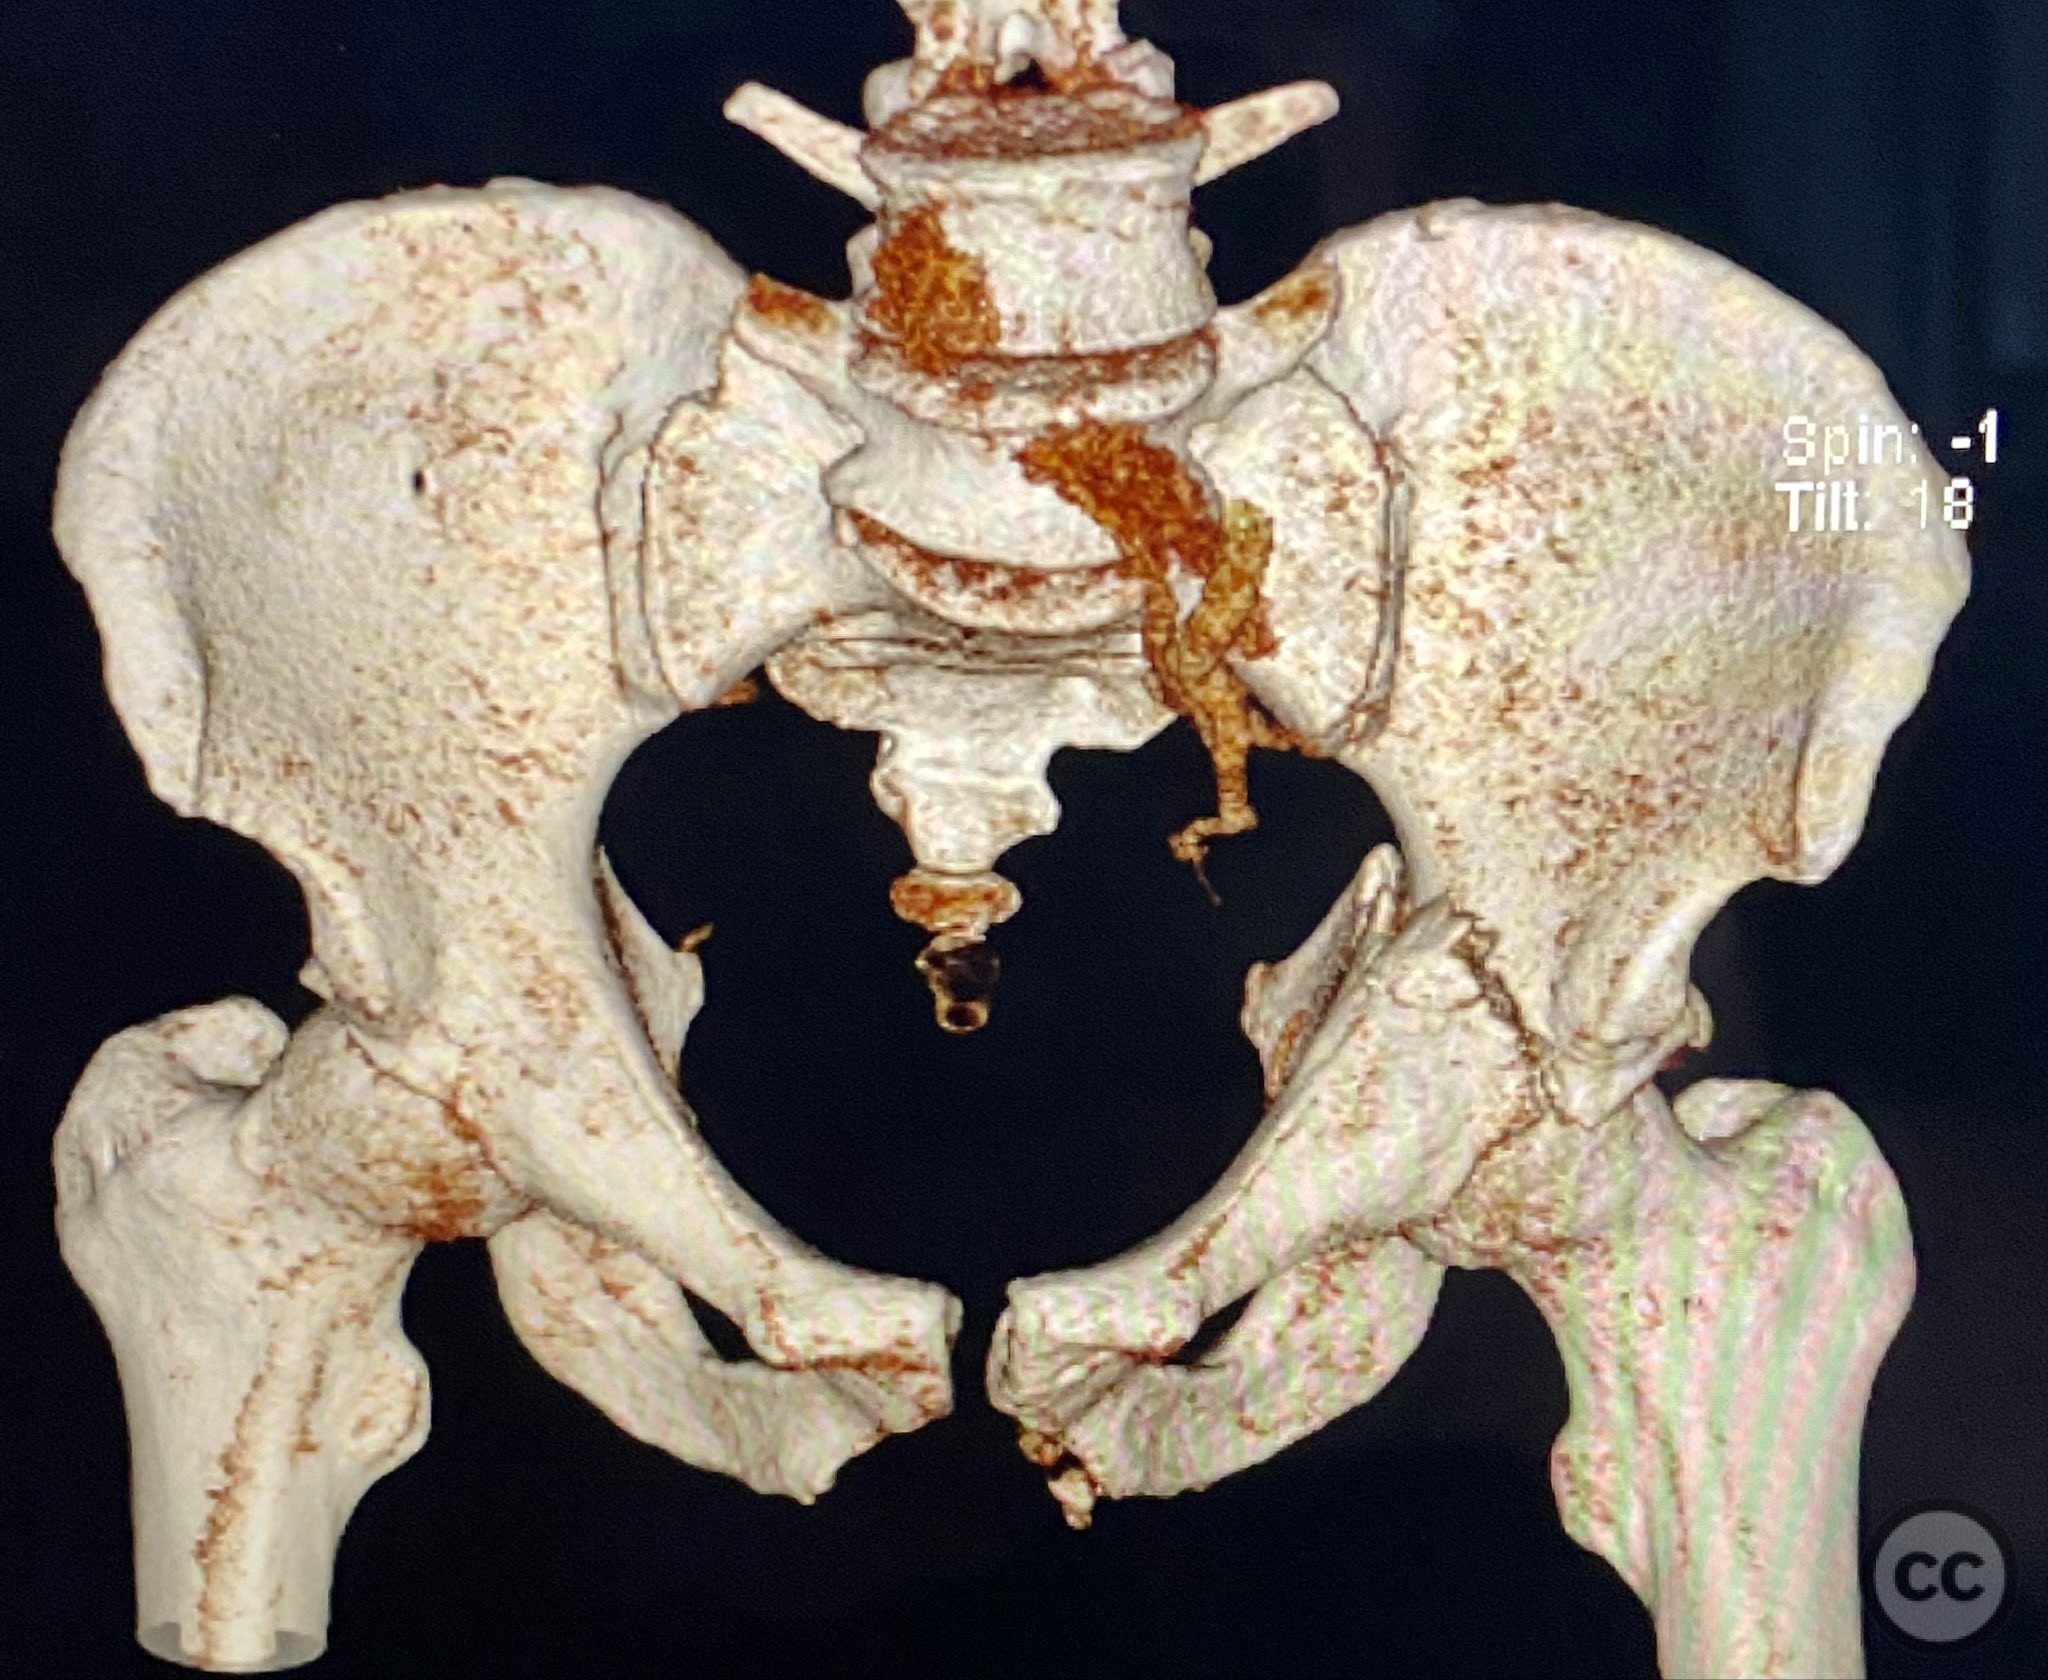

Clinical and radiological findings:  Adult male with a closed, comminuted left femoral shaft fracture and complex pelvic ring injury. Initial imaging demonstrated bilateral sacroiliac (SI) joint disruptions and a left-sided transtectal transverse acetabular fracture (Letournel-Judet: transverse type), with the fracture line exiting through the posterior wall region but without a discrete posterior wall fragment. The femoral head was displaced caudally, following the unstable distal acetabular segment, resulting in loss of congruency with the intact acetabular dome. There was also a symphyseal disruption. No associated abdominal, visceral, thoracic, cranial, or other injuries were present. Application of a circumferential pelvic binder resulted in visible changes in pelvic alignment on imaging. AO/OTA Classification: - Pelvic ring: 61-C1.3 (bilateral SI joint disruption, complete instability) - Acetabulum: 62-B1 (transverse fracture) - Femur: 32-C3 (comminuted diaphyseal fracture)

Planning remarks:  The preoperative plan involved staged management: initial resuscitation and provisional stabilization with a circumferential pelvic binder, followed by operative reduction and fixation of the pelvic ring using an anterior two-pin external fixator for SI joint compression and reduction, percutaneous iliosacral (IS) and transsacral (TS) screw fixation, and subsequent intramedullary nailing of the femur. Definitive acetabular fixation was planned via a posterior Kocher-Langenbeck approach in the prone position.

Orthopaedic implants used:   - Anterior two-pin external fixator - Percutaneous iliosacral screw(s) - Percutaneous transsacral screw(s) - Intramedullary femoral nail - 4.5 mm cortical screws (acetabular fixation) - Posterior column reconstruction plate(s)